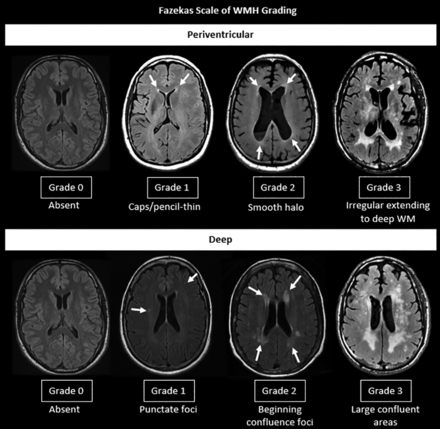

Fazekas scale of WMH grading.

WMH of presumed vascular origin are characterized by hyperintense lesions on T2 FLAIR and decreased attenuation on CT in the periventricular/deep cerebral white matter, subcortical gray matter, basal ganglia, and brainstem. Although the Fazekas visual rating scale (Fig 3) is the most commonly used method to assess the burden of WMH, there is a lack of a rigorous method to accurately quantify the WMH burden.34 Furthermore, a fronto-occipital gradient was used in few studies to describe the difference in the severity of WMH between the frontal and occipital lobes.33,35 It was suggested that patients with obvious occipital-dominant WMH were more likely to develop complications from SVD such as lobar intracranial hemorrhage than healthy controls.35 The severity of WMH is strongly associated with cerebrovascular disease, vascular risk factors, gait disturbance, cognitive symptoms, and poststroke functional outcomes.3,11

SVD MR imaging markers of the two most common etiopathogenic types of cerebral SVD in older adults, HA and CAA. BG indicates basal ganglia; EPVS: enlarged prominent perivascular spaces.

Imaging in HA versus CAA

HA (type 1) and CAA (type 2) are the most common sporadic SVD types in older adults (Fig 4 and Table 2) with intrinsically different pathophysiology, clinical significance, and prognosis.15 HA predominantly affects small perforating end arteries of the deep gray nuclei and deep white matter, whereas CAA results from β-amyloid deposition within the cortical and leptomeningeal arteries. Both types are common causes of ischemic manifestation, intracranial hemorrhage, and cognitive impairment. Although both types can be associated with similar imaging markers, including CMB, WMH, lacunar infarcts, and PVS, the anatomic distribution of these markers can be helpful to differentiate these 2 entities radiologically. Lobar/superficial and cortical distribution is consistently associated with CAA, whereas the involvement of deep brain regions and the basal ganglia is most often associated with HA (Fig 4 and Table 2).15,33,36,42⇓-44 Furthermore, deep CMB are typically associated with arteriolosclerosis, whereas a strictly superficial/lobar location is characteristic of CAA.10 CAA is characteristically associated with lobar CMV, cSS, centrum semiovale perivascular spaces, and multiple punctate FLAIR WMH (typically >10) with a predilection for the posterior regions.15,33,44 A peri-basal ganglia pattern of WMH is strongly linked to arteriolosclerosis (Fig 4).15